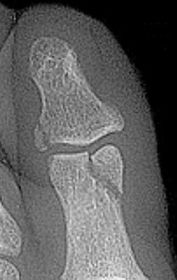

Describe what is occurring at the head of the 3rd met | Freiberg’s infarction (avascular necrosis of the metatarsal head) |